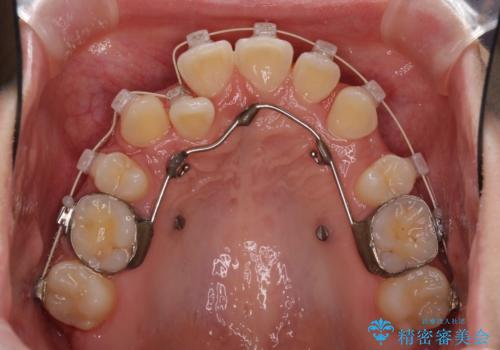

インビザラインが続けられない ワイヤー矯正での抜歯矯正 その2

- 八重歯やデコボコをインビザラインで治療したいとのことで来院された患者様です。

インビザライン単体で治療を行うには叢生が強いと判断されたため、事前にワイヤー装置で抜歯矯正を行い、ある程度改善してからインビザラインにて仕上げていくこととしました。